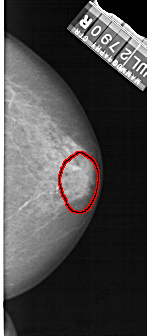

A_1302_1.RIGHT_CC

FILE: A_1302_1.RIGHT_CC.OVERLAY

TOTAL_ABNORMALITIES 1

ABNORMALITY 1

LESION_TYPE CALCIFICATION TYPE PUNCTATE-AMORPHOUS DISTRIBUTION REGIONAL

ASSESSMENT 4

SUBTLETY 3

PATHOLOGY BENIGN

TOTAL_OUTLINES 1

BOUNDARY